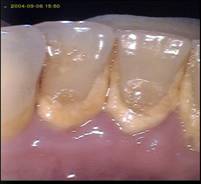

- du tartre supra gingival (visible sur les dents)

Le tartre se forme de préférence dans les zones en regard des glandes salivaires, c’est-à-dire sur la face linguale des incisives inférieures, coté labial des molaires supérieures.

Le tartre est rugueux et poreux. Il permet la rétention de nouvelle plaque, qui a son tour va se calcifier et venir augmenter la couche de tartre existant.

Enseignement du brossage

Le tartre se forme prioritairement au niveau de la face linguale (du côté de la langue) des incisives inférieures ; ensuite on peut l'observer sur la face vestibulaire (du côté de la joue) des premières molaires supérieures. Il se dépose plus rarement ailleurs, mais on peut parfois en observer sur toutes les dents.